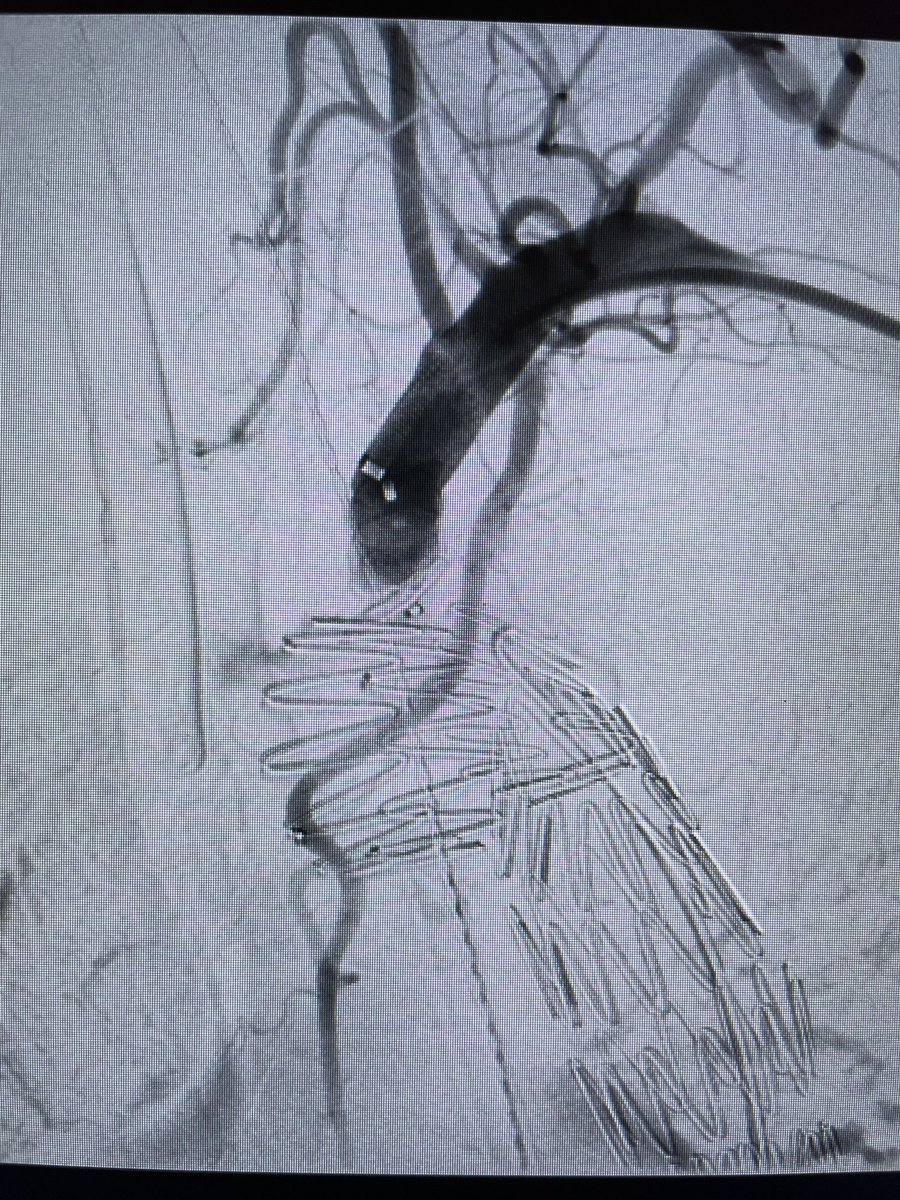

Impending rupture sp fenestrated repair (pain, rapid sac growth) from 1b and psb 1c endoleak. Tx with CA/SMA branch extension/angioplasty and iliac branch device (2/2 size). Cedars-Sinai Division of Vascular Surgery Vascular Surgery Associates Rameen S. Moridzadeh, MD Department of Surgery at Cedars-Sinai #aortaed #VascSurg #vasculartwitter